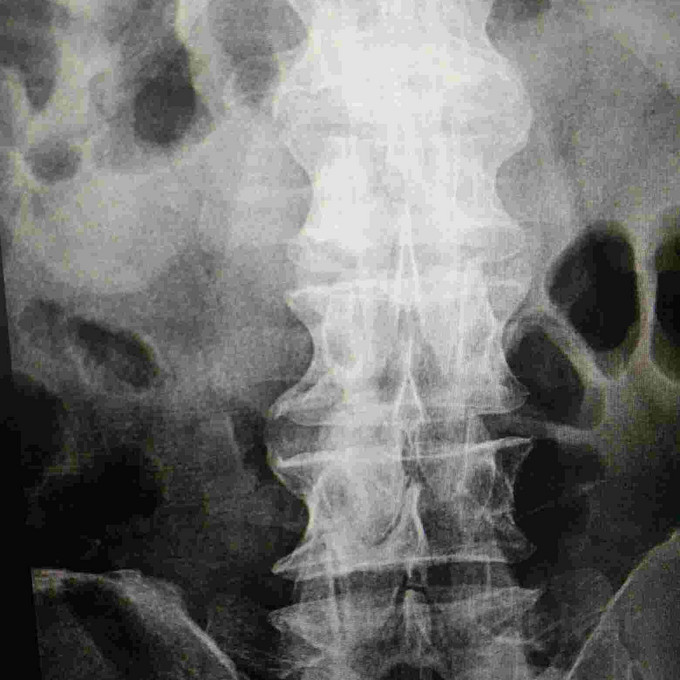

腰椎正侧位片描述?

患者男,59岁,腰痛1年来就诊,行腰椎正侧位片(见图),因我基层医院刚刚开展Dr摄影技术,且缺乏有资质的影像诊断医师,在描述和诊断此片时遇到难题,望贵人指教,谢过!